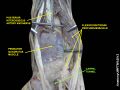

The tendons of the flexor digitorum superficialis and profundus pass through a common ulnar sheath, while the tendon of the flexor pollicis longus passes through a separate radial sheath. The mesotendon shared by these tendons is attached to the radial and palmar walls of the carpal tunnel.[4]

Superficial to the carpal tunnel and the flexor retinaculum, the ulnar artery and ulnar nerve pass through the ulnar tunnel/Guyon's canal.[4]

Ten structures pass through the carpal tunnel, most of them flexor tendons[2] (not the muscles themselves):

- flexor digitorum profundus (four tendons)

- flexor digitorum superficialis (four tendons)

- flexor pollicis longus (one tendon)

- Median nerve between tendons of flexor digitorum profundus and flexor digitorum superficialis

The flexor carpi radialis (one tendon) is often incorrectly stated to travel within the carpal tunnel. More precisely, it travels within the fibers of the flexor retinaculum which forms the roof of the carpal tunnel, rather than running inside the tunnel itself.